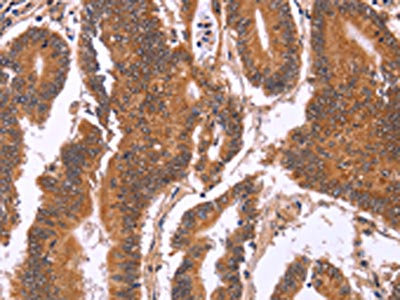

The image on the left is immunohistochemistry of paraffin-embedded Human cervical cancer tissue using CSB-PA591907(CDC37L1 Antibody) at dilution 1/60, on the right is treated with fusion protein. (Original magnification: ×200)

The image on the left is immunohistochemistry of paraffin-embedded Human colon cancer tissue using CSB-PA591907(CDC37L1 Antibody) at dilution 1/60, on the right is treated with fusion protein. (Original magnification: ×200)